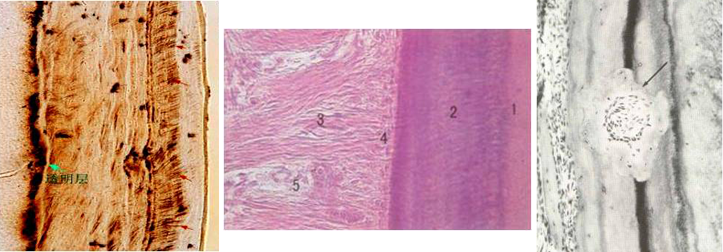

牙骨质的组织学结构与密质骨相似,由细胞和矿化的细胞间质组成。细胞位于陷窝内,并有增生沉积线。但不同于骨的是牙骨质无哈佛管,也无血管和神经。

◇ 无细胞牙骨质和细胞牙骨质,无细胞牙骨质(acellularcementum)也称原发性牙骨质,紧贴于中间牙骨质表面,主要由牙骨质层板构成而无细胞。分布于自牙颈部到近根尖l/3处,牙颈部往往全部由无细胞牙骨质所占据。牙骨质是分层形成的,新的一层沉积在先前的一层上,构成牙骨质层板。在脱钙切片上可较清楚地显示牙骨质分层的生长线。形成速度较快的牙骨质表面有一层刚形成尚未钙化的牙骨质即类牙骨质(cementoid)。形成速度慢者,如在牙颈部无类牙骨质。无细胞牙骨质的主要功能是提供牙与牙周组织的附着。

细胞牙骨质(cellular cementum)也称继发性牙骨质,常位于无细胞牙骨质的表面,或者细胞牙骨质和无细胞牙骨质交替排列。但在根尖部1/3可以全部为细胞牙骨质。细胞牙骨质主要起适应性作用,对牙的磨耗。移动做出反应,也与牙及牙周组织的修复有关。

成熟牙骨质中的细胞称为牙骨质细胞,位于牙骨质基质陷窝内。类似于骨细胞。细胞体积较小,细胞表面有许多细小胞质突起向牙周膜方向伸展,借以从牙周膜吸取营养,邻近的牙骨质细胞突起可相互吻合。电镜下可见细胞器较稀疏,内质网可扩张,线粒体稀少。细胞在间质中占据的空间称为陷窝,突起占据的空隙称小管。在牙磨片中,由于细胞破坏、消失,故镜下所见为陷窝与小管。更深部的细胞则因营养吸收困难而明显变性或细胞消失,陷窝也可变空。

牙骨质细胞间质内的纤维主要由成牙骨质细胞和牙周膜成纤维细胞产生的胶原纤维所构成。前者纤维排列与牙根表面平行,后者又称为穿通纤维(perforating fiber)或沙比纤维(Sharpey’s fiber),与牙根表面垂直并穿插于其中。基质主要由蛋白多糖等和矿物盐组成,后者以磷灰石晶体的形式沉积在胶原纤维上形成钙化的基质。

◇ 牙本质牙骨质界(dentino-cemental junction) 牙本质和牙骨质是紧密结合的,光镜观呈现一较平坦的界线,但电镜下可见该处牙本质和牙骨质的胶原原纤维互相缠绕。

◇ 牙骨质的表面特点,牙骨质将牙周膜的纤维附着于牙体,因此表面有许多纤维束,分布于整个牙根表面。纤维的分布可呈不均匀性。有些纤维束埋入牙骨质较深,有些较浅。一般情况下,牙骨质越薄,纤维埋入得越浅。这些穿通纤维较骨中的穿通纤维束小。牙骨质表面有时可见吸收区。当吸收停止后,有些吸收区发生牙骨质的修复,这是牙骨质的重要特性。在吸收前沿和修复性牙骨质之间可见反转线(reversal line),意思是吸收过程得到了逆转。乳牙脱落的过程中出现牙根吸收,同时可见局部牙骨质修复现象。这种修复可能在乳牙持续性脱落过程中,给予乳牙某种支持。